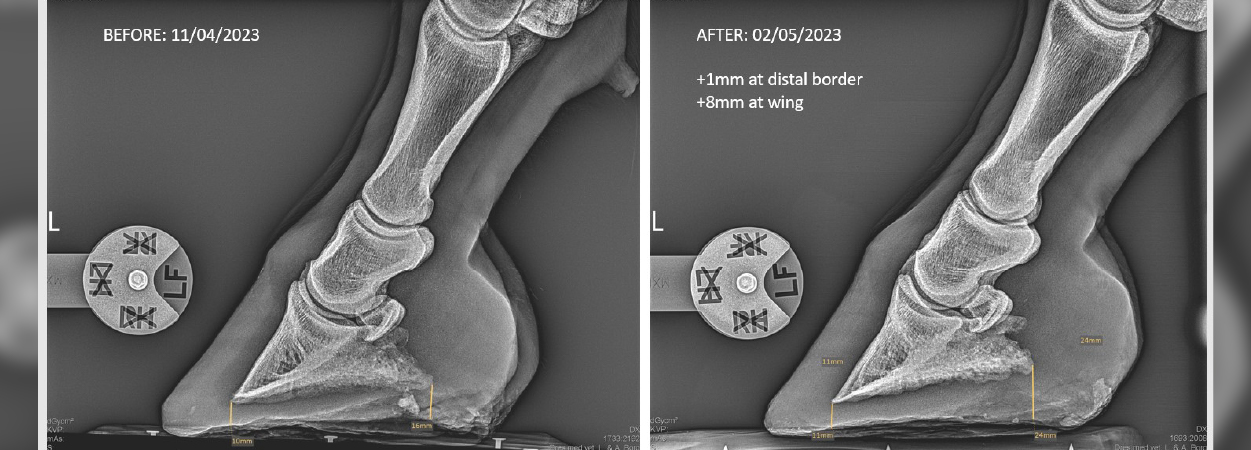

Sarah Albanozzo, a Maltese, part-time student researcher with the Royal (Dick) School of Veterinary Studies, funded and coordinated this study which has shown promising developments. Three adult geldings and one adult mare participated in the research project. Two were horses of 550kg ± 50 kg and two were Shetland ponies (one mare) of 200kg ± 20kg. Ages ranged from 8-20 years (mean age: 14 years) and body condition scores were 6 (scale 1-9). A health check on all was conducted by an equine veterinarian prior to and following the study. A day before the experiment, all equine hooves were radiographed from the lateral side to ensure adequate sole depth and correct alignment of the phalanges. Sole depth was measured from the coffin bone - distal border (crena) and from the wing (angle). Radiographs of all hooves were again taken 3 days following the experiment to measure sole thickness.

External measurements of each hoof were recorded from day 1 to day 9 to monitor hoof growth in particular areas, from the solar side: (a) distance from frog apex to toe; (b) collateral groove depth at mid-bar, (c) collateral groove depth at apex, (d) heel height, (e) frog width, and from the dorsal side (f) distance from coronet to toe.